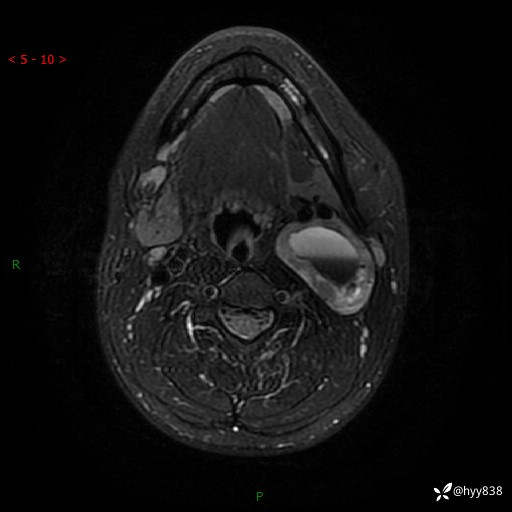

年轻小伙,发现左侧颈部肿物3年余,逐渐增大---结果公布~

现病史:患者约3年前因感冒发现左侧颈部长一肿物,约半个鸡蛋大小,无明显疼痛及其他不适,一直未行特殊处理。3个月前发现左侧颈部肿物变大,随后至当地市第二人民医院耳鼻喉科行左侧颈部彩超示:左侧颈部囊实混合性包块;喉部MPR示:左侧胸锁乳突肌内前方占位,累及左侧喉旁间隙,建议增强扫描。建议手术治疗。患者考虑。随后至我院肿瘤科就诊,行细胞学穿刺示:考虑血管源性肿瘤可能,建议进一步检查。建议至我院口腔科就诊,行颌面部MRI示:左侧颌下腺后方团状异常信号灶,建议增强。建议手术治疗。为求进一步治疗,门诊以“左侧颈部肿物”收入院。 起病以来,患者神志清、精神良好,饮食睡眠良好,大小便正常,体重未见明显变化。

颈部MRI平扫+增强